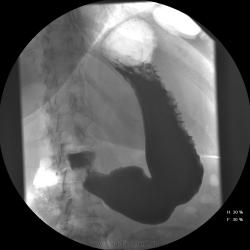

Женищина 49 лет, повышенного питания, обратилась с жалобами на потерю аппетита, жжение после чуть острой пищи, отрыжку с неприятным запахом, иногда темный стул, несколько похудела. Данные жалобы с сентебря-октября. Никуда не обращалась, коррегировала питанием. В последнее время стало хуже, обратилась...

Привратник удлиннен и ригиден, такое бывает при раке. Рек. ЭГДС.

Вы правы. я несколько недорасказал. женщина пришла уже с фгдс - инфильтративно-язвенный процесс в выходном отеде желудка у привратника по малой кривизне с переходом на переднюю стенку. так что прицельно смотрел этот отдел. перистальтка была ослаблена, краевой дефект в препилорической зоне по малой кривизне, передней стенке, кажущееся удлинение привратника, нависание основания луковицы - вообщем как в книжке. эвакуация было не изменена. написал рак выходного отдела желудка. вчера пришла гистология - высокодиф-я аденокарцинома. вот такая история.

Пока, касаясь только луковицы, но не препилорического отдела. "Ниши" в луковице есть, и они нуждаются в объяснении.

Конечно, в пилорическом канале уже растет, и "это" растет, уже и препилорической части и в луковице 12-ти перстной кишки.